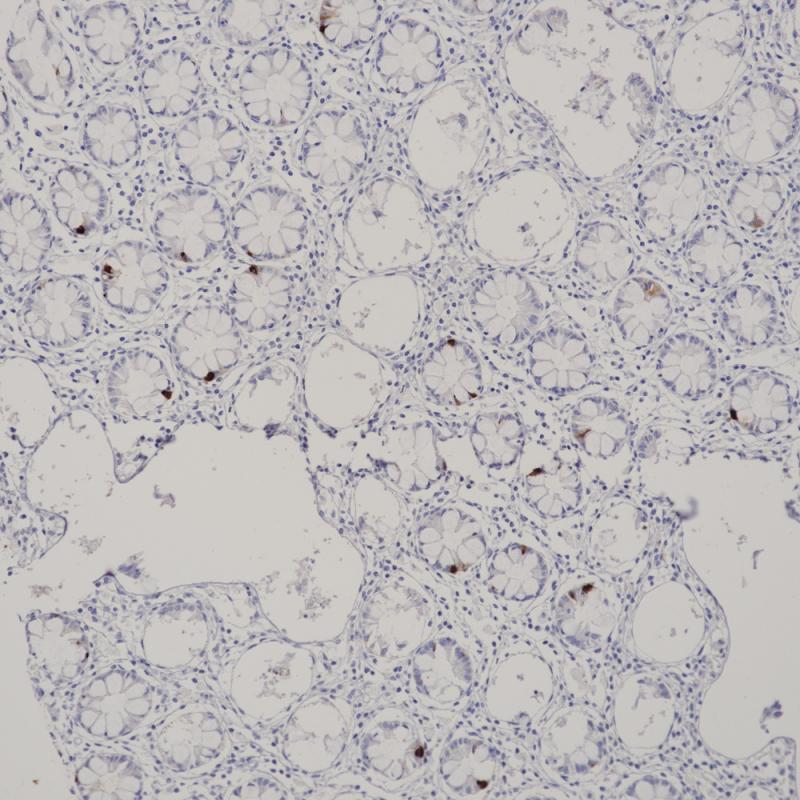

Arginase-1也称作肝型精氨酸酶,它作为尿循环的一个关键酶,在正常肝组织的肝细胞中的表达具有很高的特异性,胆管上皮细胞、肝窦内皮细胞、枯否细胞及血管内皮细胞均不表达。在肝细胞癌诊断中,分化良好及中度分化的肝细胞癌其表达率高达100%和92%,低分化肝细胞癌相对较低,其敏感性高于HepPar1和Glypican3.

细胞质/细胞核